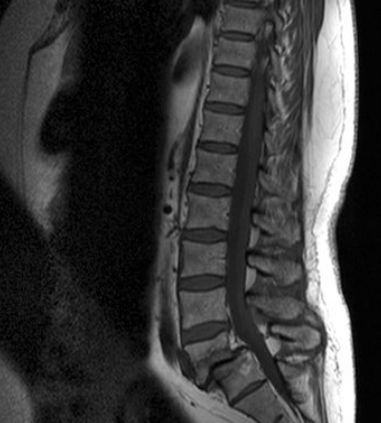

矢状面是将人体分为左、右两部分的切面。下图是腰椎的一个MRI的矢状面图。